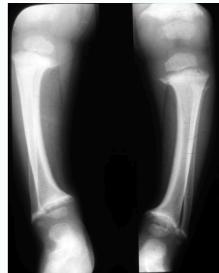

- Widened physis (epiphyseal growth plate)

- Cupping of metaphyseal end (weak new bone)

- Irregular metaphyseal end

- Osteopenia (decreased bone density)

- Thin cortex

- Deformity

Lower Limb Deformities

- Bowing of legs: most common presentation

- Localized – distal tibiae most affected

- Widened physis (first and most prominent finding)

- Metaphyseal changes:

- Cupping (due to weak new bone)

- Irregular margins

- Deformed bones